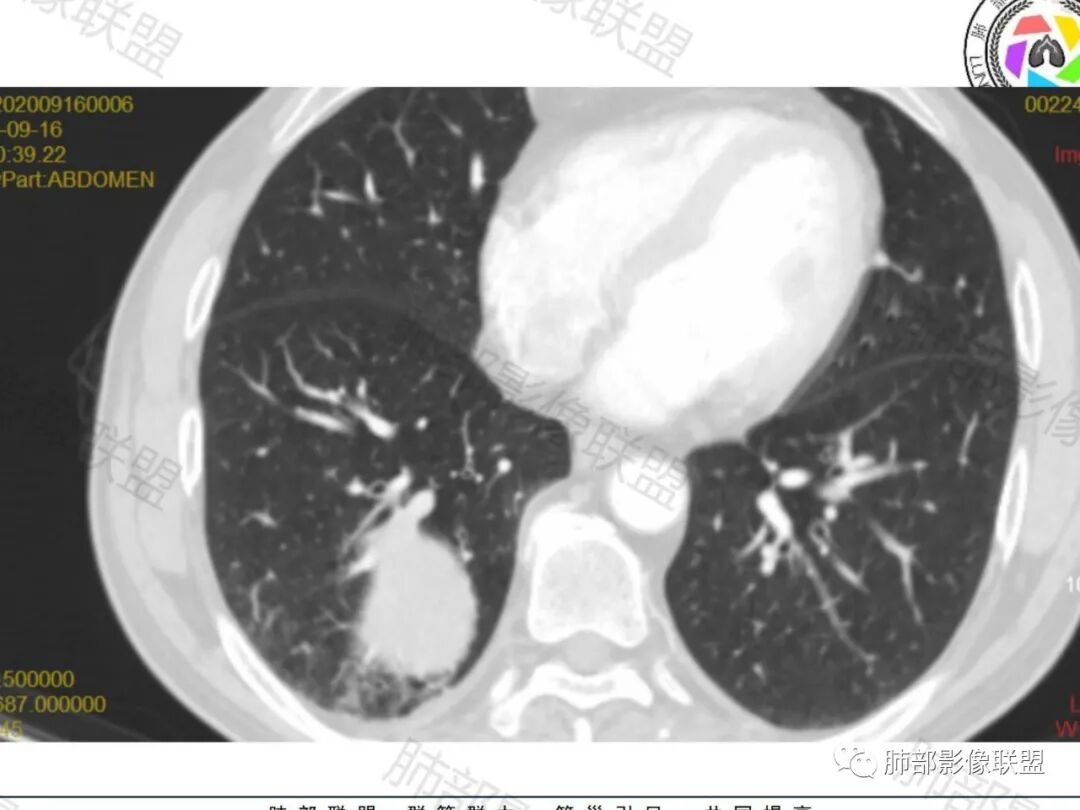

右肺下叶一类圆形肿块影,内缘边缘光滑,外缘边界模糊,可见磨玻璃影,整体以彭隆为主,部分边缘包绕支气管,平扫密度尚均匀,增强后不均匀强化,部分与膈肌黏连,临床,62岁男性,无症状,考虑恶性:腺癌,鳞癌,神经内分泌癌,肉瘤

老年人,偶然发现,右肺下叶类圆形软组织占位,密度较均匀,病灶边缘光滑,无毛刺分叶,支气管血管受挤压向外移位,增强病灶强化较均匀。考虑恶性肿瘤,外向内生长,肉瘤,肉瘤样癌,癌肉瘤,其次神经内分泌癌。

老年男性,右肺下叶软组织肿物,整体外形光整,周围组织推挤,可见血管贴边,貌似又有血管进入,整体强化均匀,考虑良性可能大,硬化性肺细胞瘤?鉴别sft

老年男性,偶然发现,说明平时没有症状,边缘光整,血管贴边,整体强化均匀,倾向于良性或者低度恶性(PSP?类癌?)

老年男性,肿瘤标志物高,右肺占位,边界清楚,内部密度均匀,坏死不明显,无明显分叶,血管贴边,考虑PSP,老年男性,肿块大,需鉴别恶性,肉瘤样癌?高分化鳞癌?

男性,62,胆结石入院胸部CT偶然发现占位。肿标稍增高,右肺下叶胸膜下肿块,边缘尚清,密度较均匀,增强明显强化,血管贴边,空气新月征?静脉期可见低强化区,首先考虑PSP,鉴别肉瘤样癌及神经内分泌肿瘤

老年男性,右肺下叶肿块,边缘光整,血管贴边,部分血管进入,整体强化尚均匀,考虑大细胞癌,鉴别PSP、SFT

右肺下叶类圆形软组织肿块,病灶边缘光滑,无明显毛刺分叶,支气管受压推移,血管贴边,部分血管进入病灶,增强病灶强化不均匀,内可见低密度,病灶与右侧膈肌分界不清,考虑神经内分泌肿瘤,大细胞癌。鉴别PSP

老年男性,肿瘤标志物高,右肺下叶类圆形肿块,宽基底与胸膜相连,边缘光整,密度均匀,周围气管及血管受压推移,延迟强化,其内见纤细血管,似有小低密度灶,首先考虑间叶组织恶性肿瘤,良性平滑肌瘤、纤维瘤不除外

患者中老年男性,检查发现右下肺占位。查肺癌标记物稍有升高。血常规白细胞计数稍降低。胸部CT:右肺下叶后基底段类圆形肿块,边缘光滑,边界清楚,周边见气管受压扩张,增强轻度强化,内见点状低密度影,见血管贴边。综合考虑良性过低度恶性病变,PSP可能,其它恶性肿瘤待排。

支气管,血管均受压推移,类圆形占位,无分叶,无毛刺,光滑表面,明显均匀强化,倾向于psp,鉴别错构瘤,肉瘤,肉瘤样癌,类癌等神经内分泌肿瘤,转移,imt。

老年男性,右肺下叶软组织肿块,边缘光滑,血管和支气管贴边,肿块与膈肌分界不清,增强后不均匀强化,可见点片状低密度影,考虑良性或低度恶性肿瘤,psp,神经内分泌肿瘤

右肺下叶大肿块,血管贴边,部分小分支进入肿块内,密度略欠均匀,边缘总体光滑,支气管关系不明确,老年人,总体考虑恶性,nse高,首先考虑神经内分泌癌,鉴别肉瘤,转移瘤

右下肺大团块,边界较清,病灶内有血管影,小灶低密度,胸膜下脂肪清晰,需要薄层确定肺血管有没穿行,疾病谱:神经内分泌癌(大 类),SFT,PSP,肉瘤样癌,间叶肿瘤,考虑神经内分泌癌(大 类)>sft>psp>肉瘤样癌

老年男性,NSE高。右肺下叶软组织肿块,平扫密度均匀,增强后不均匀强化,其内似可见小血管影。肿块边缘光滑,无分叶无毛刺,血管和支气管贴边。考虑神经内分泌肿瘤,鉴别:psp

老年男性,检查发现右下肺占位。CT:右肺下叶一类圆形肿块影,膨隆,无分叶,边缘基本光滑,近端支气管推挤狭窄,与胸膜夹角为锐角,增强见不均匀强化,未见坏死,近端见血管贴边,胸壁脂肪间隙清楚。考虑良性病变——PSP可能性大。鉴别神经内分泌癌、肉瘤、SFT。

右肺下叶软组织肿块,边缘光滑,临近血管受压变形且增粗,增强后见斑片状低强化区,界不清,实性部分见条状血管影,边缘光滑,考虑PSP可能,肿块与支气管关系不密切,腺癌,腺鳞癌不符合,肿块内增强后血管走形自然,间叶组织起源肉瘤不符

有意思的病例,男性,右肺下叶肿块,强化中等,血管贴边,肿标高,考虑低度恶性肿瘤,神经内分泌肿瘤,类癌最可能,别的感觉都要往后放,PSP,我三十五例病例,男性只有3例,比例太低了,而且强化幅度也偏低,而且肿瘤标志物好几个高的,只敢放第二位了

右肺下叶肿块,呈外带大内带小的椭圆形改变(内带受支气管及血管挤压原因),边缘光滑,无分叶毛刺,支气管受压,增强后,均匀延迟强化,动脉期见血管贴边,静脉期内部瘤样血管强化区,相邻胸膜无侵犯,纵隔无淋巴结肿大,符合PSP,不鉴别。

老年男性,肿瘤标志物高,右下肺占位性病变,密度均匀,其内无明显坏死,均匀强化,无毛刺分叶,考虑硬化性肺细胞瘤,鉴别肉瘤样癌

老年男性,右肺下叶肿块,边界光滑,血管贴边,部分小分支进入,肿块内可见增粗血管,肿瘤指标偏高,总体考虑恶性,不典型类癌?大细胞癌?鉴别PSP。

胸部CT:右肺下叶一类圆形肿块影,边界清楚,大部分边缘光滑、外缘边界模糊,邻近支气管推移、血管贴边,病灶内可见分枝状血管,平扫密度尚均匀,增强后大部分均匀延迟强化,部分与膈肌黏连、尾征?考虑:类Ca>PSP>SFT。鉴别肉瘤样Ca,CD等。

肿块位于周围(起自细支气管呼吸道上皮),均匀膨胀生长(符合良性的生长特点),病灶内部大部分密度较均匀,部分小低密度不强化区(囊变),增强强化较明显,边缘血管增粗贴边,临近支气管受压,支持PSP。